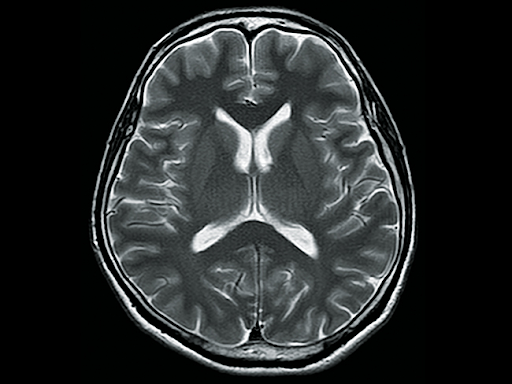

Аппарат укомплектован коротким сверхпроводящим постоянным магнитом с напряженностью 1.5T и активной экранирующей системой. Обеспечивает качественные изображения и самое большое поле обзора среди аналогичных устройств — 55×55×50 см.

Технология Advanced intelligent Clear-IQ Engine позволяет получать МР-изображения с безупречной детализацией структур. Нейронная сеть реконструирует данные с низким отношением «сигнал/шум», улучшая SNR изображений.

Advanced intelligent Clear-IQ Engine (AiCE)